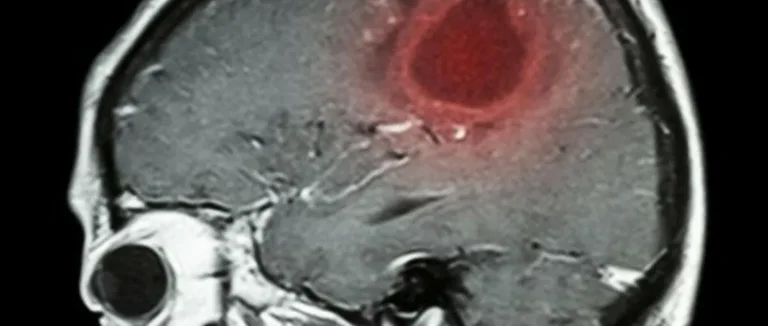

L'IRM Fonctionnelle (IRMf)

L'IRM fonctionnelle (IRMf) détecte les changements dans le flux sanguin liés à l'activité neuronale. Elle cartographie les régions du cerveau actives, que ce soit lors de tâches ou au repos. L'IRMf aide à comprendre comment notre cerveau se concentre.

Les avantages de l'IRMf sont :

● Une haute résolution spatiale

● La capacité de cartographier l'activité cérébrale en temps réel

● Une méthode non invasive

Potentiel pour la Médecine Personnalisée

La technologie Mind Scan pourrait changer la médecine personnalisée. Les scans cérébraux pourraient aider à diagnostiquer et traiter plus précisément. Cela permettrait des interventions plus efficaces.

Les données de ces technologies pourraient aussi aider à créer des plans de traitement sur mesure. Cela améliorerait les résultats pour les patients.